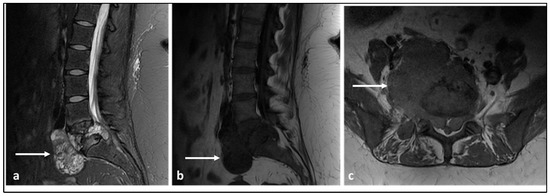

| Ewing sarcoma | Lytic lesion. Vertebral collapse. | Low to intermediate signal T1 and intermediate to high signal T2 lesion. Enhancing extra-osseous soft tissue component. |